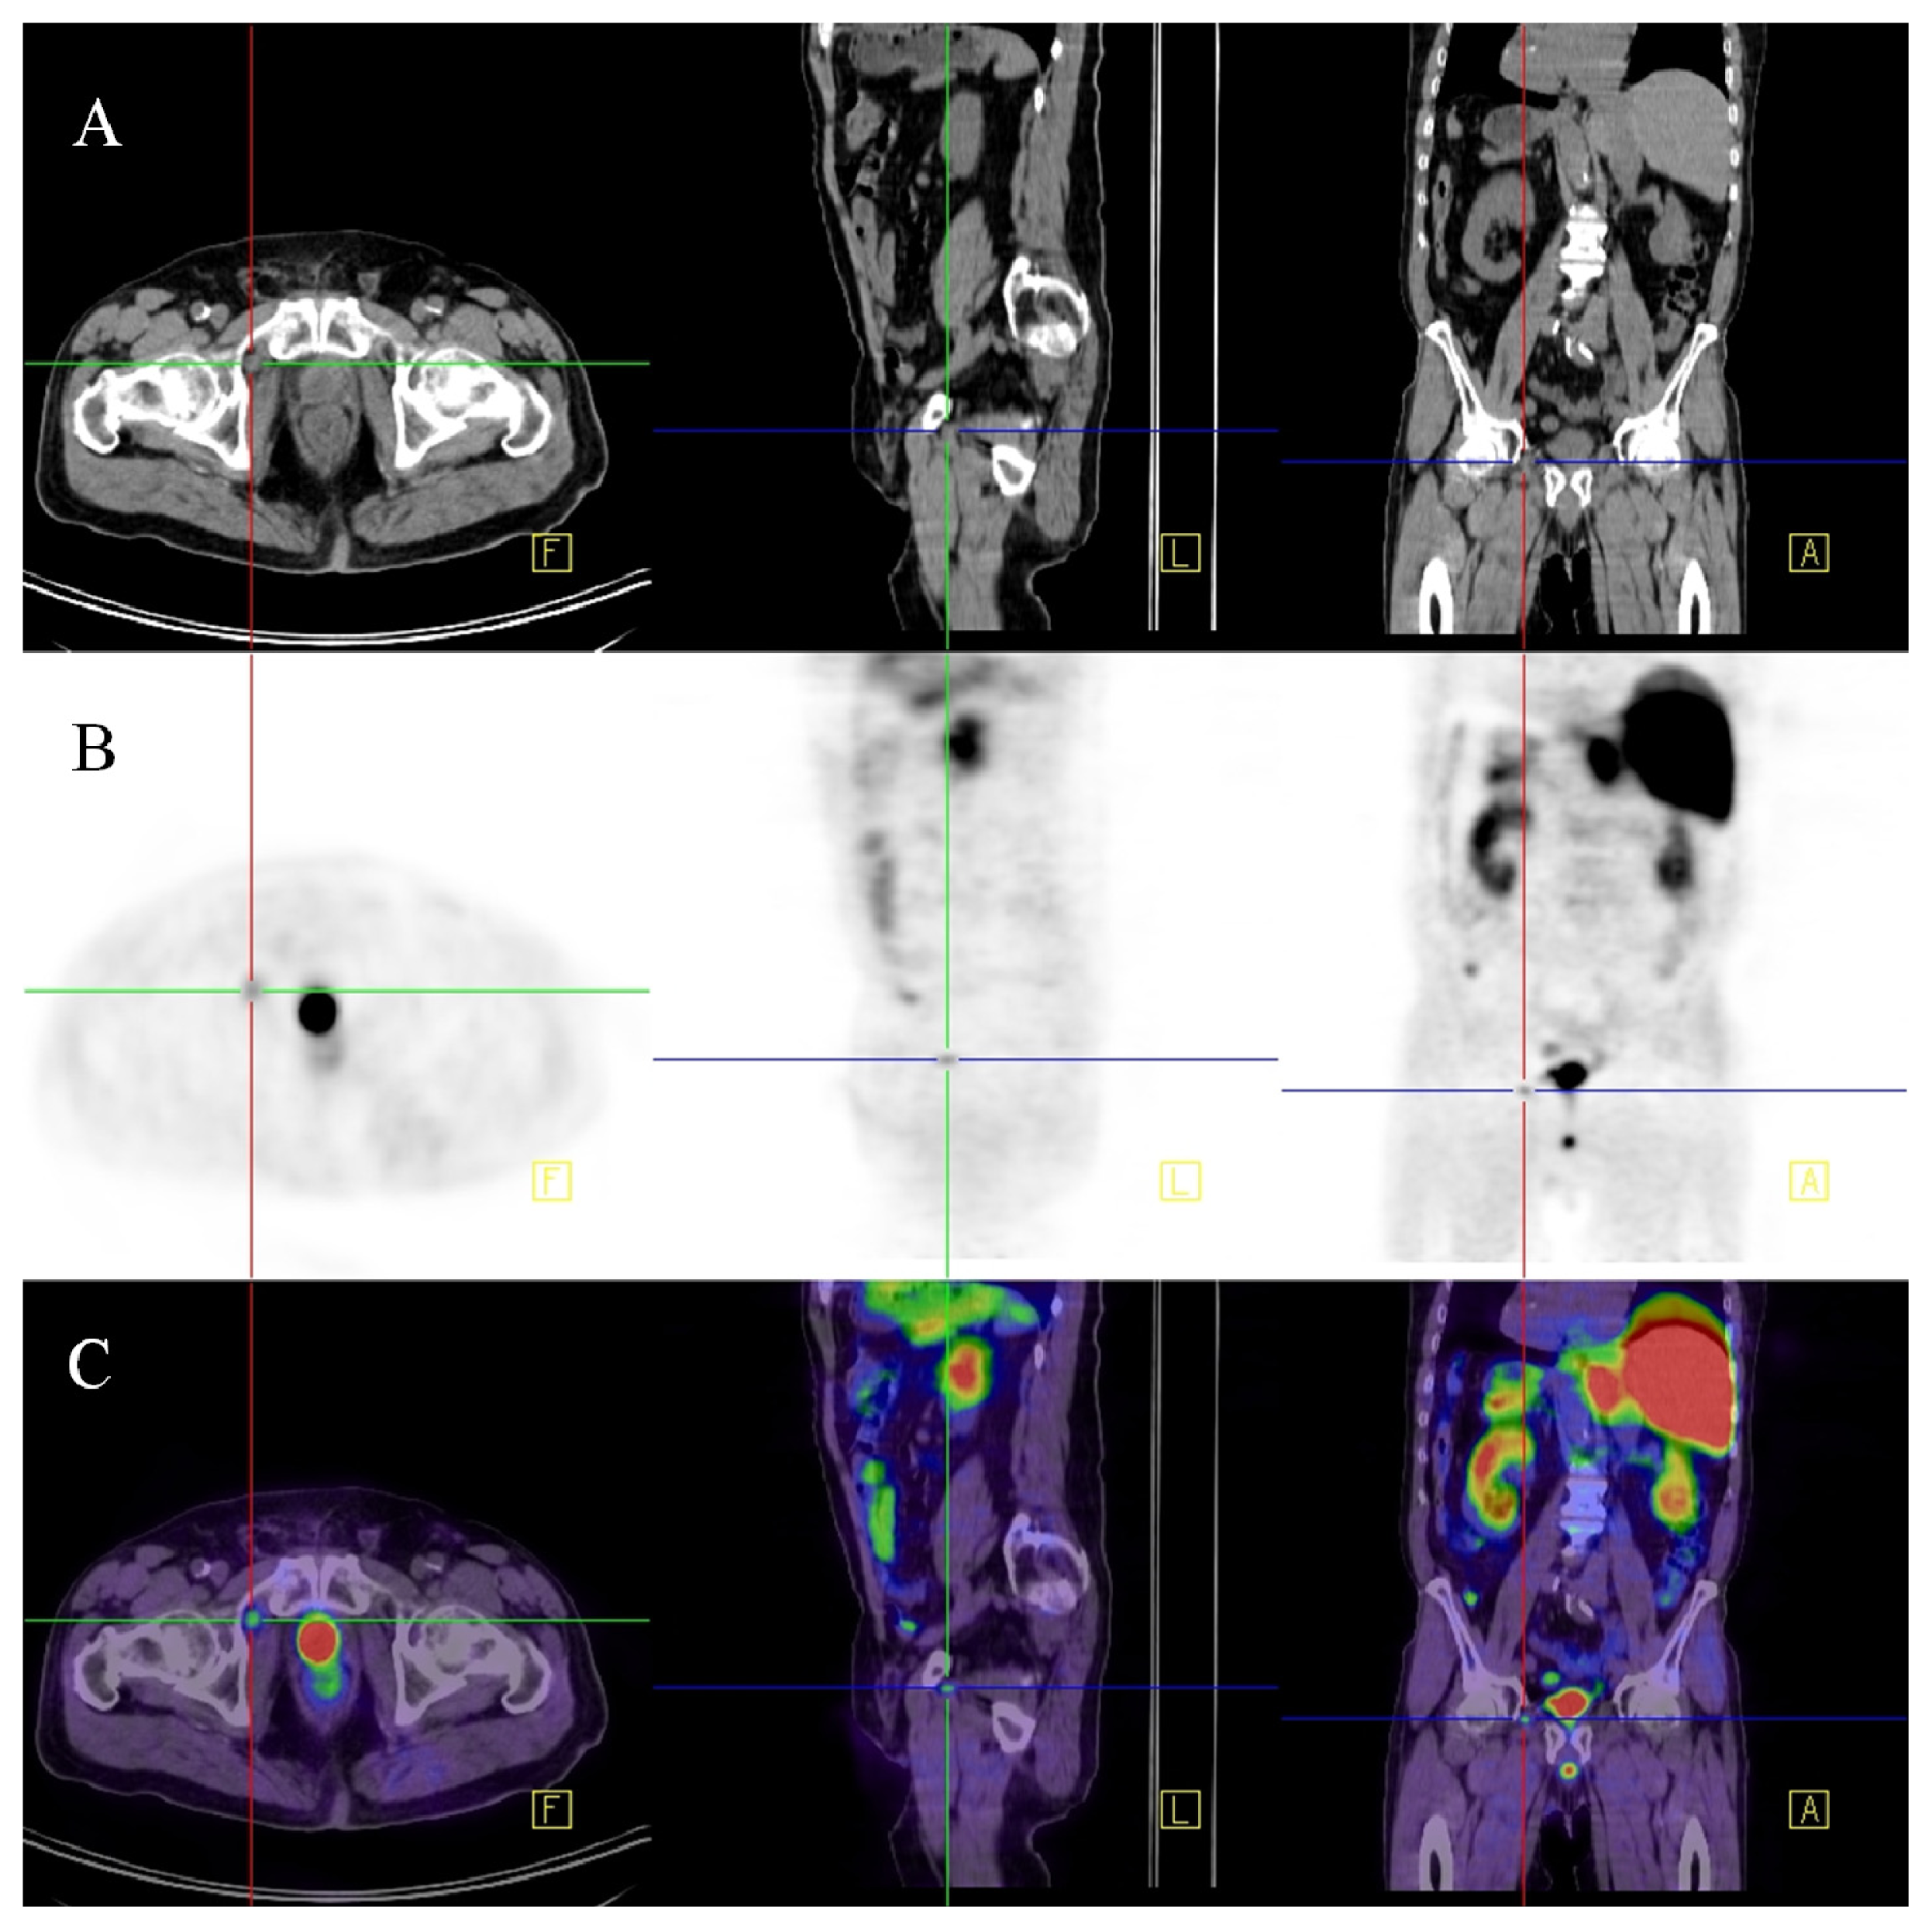

Afshar-Oromich et al. showed promising results in an initial study in 37 patients. They observed excellent contrast uptake, also in small lymph nodes (see Figure 2) [43]. In direct comparison to 18F labeled Choline, first results suggest that PSMA-targeted imaging performs better in detection of small lymph nodes in patients with low PSA values [44]. If these results are reproducible this may have significant clinical impact on diagnosing prostatic lymph node metastases.

Figure 2.

68Ga-PSMA-PET-CT. Patient with prostate cancer (status after brachy-therapy and bilateral iliac lymph node dissection, current PSA 21 μg/L). PET images were acquired after the administration of 68GA-PSMA-Ligand (60 min thereafter). The figure shows fused images (PET-CT): On the coronal view (A) a pathologic isotope uptake in multiple lymph nodes in the right para-iliac region and infra-carinal (mediastinum) is clearly visible; the corresponding transversal images show the para-iliac (B) and infra-carinal (C) lymph nodes with elevated uptake of the tracer. The corresponding transversal native CT images present these suspect structures (D,E) as normal sized lymph nodes (marked by red arrows).